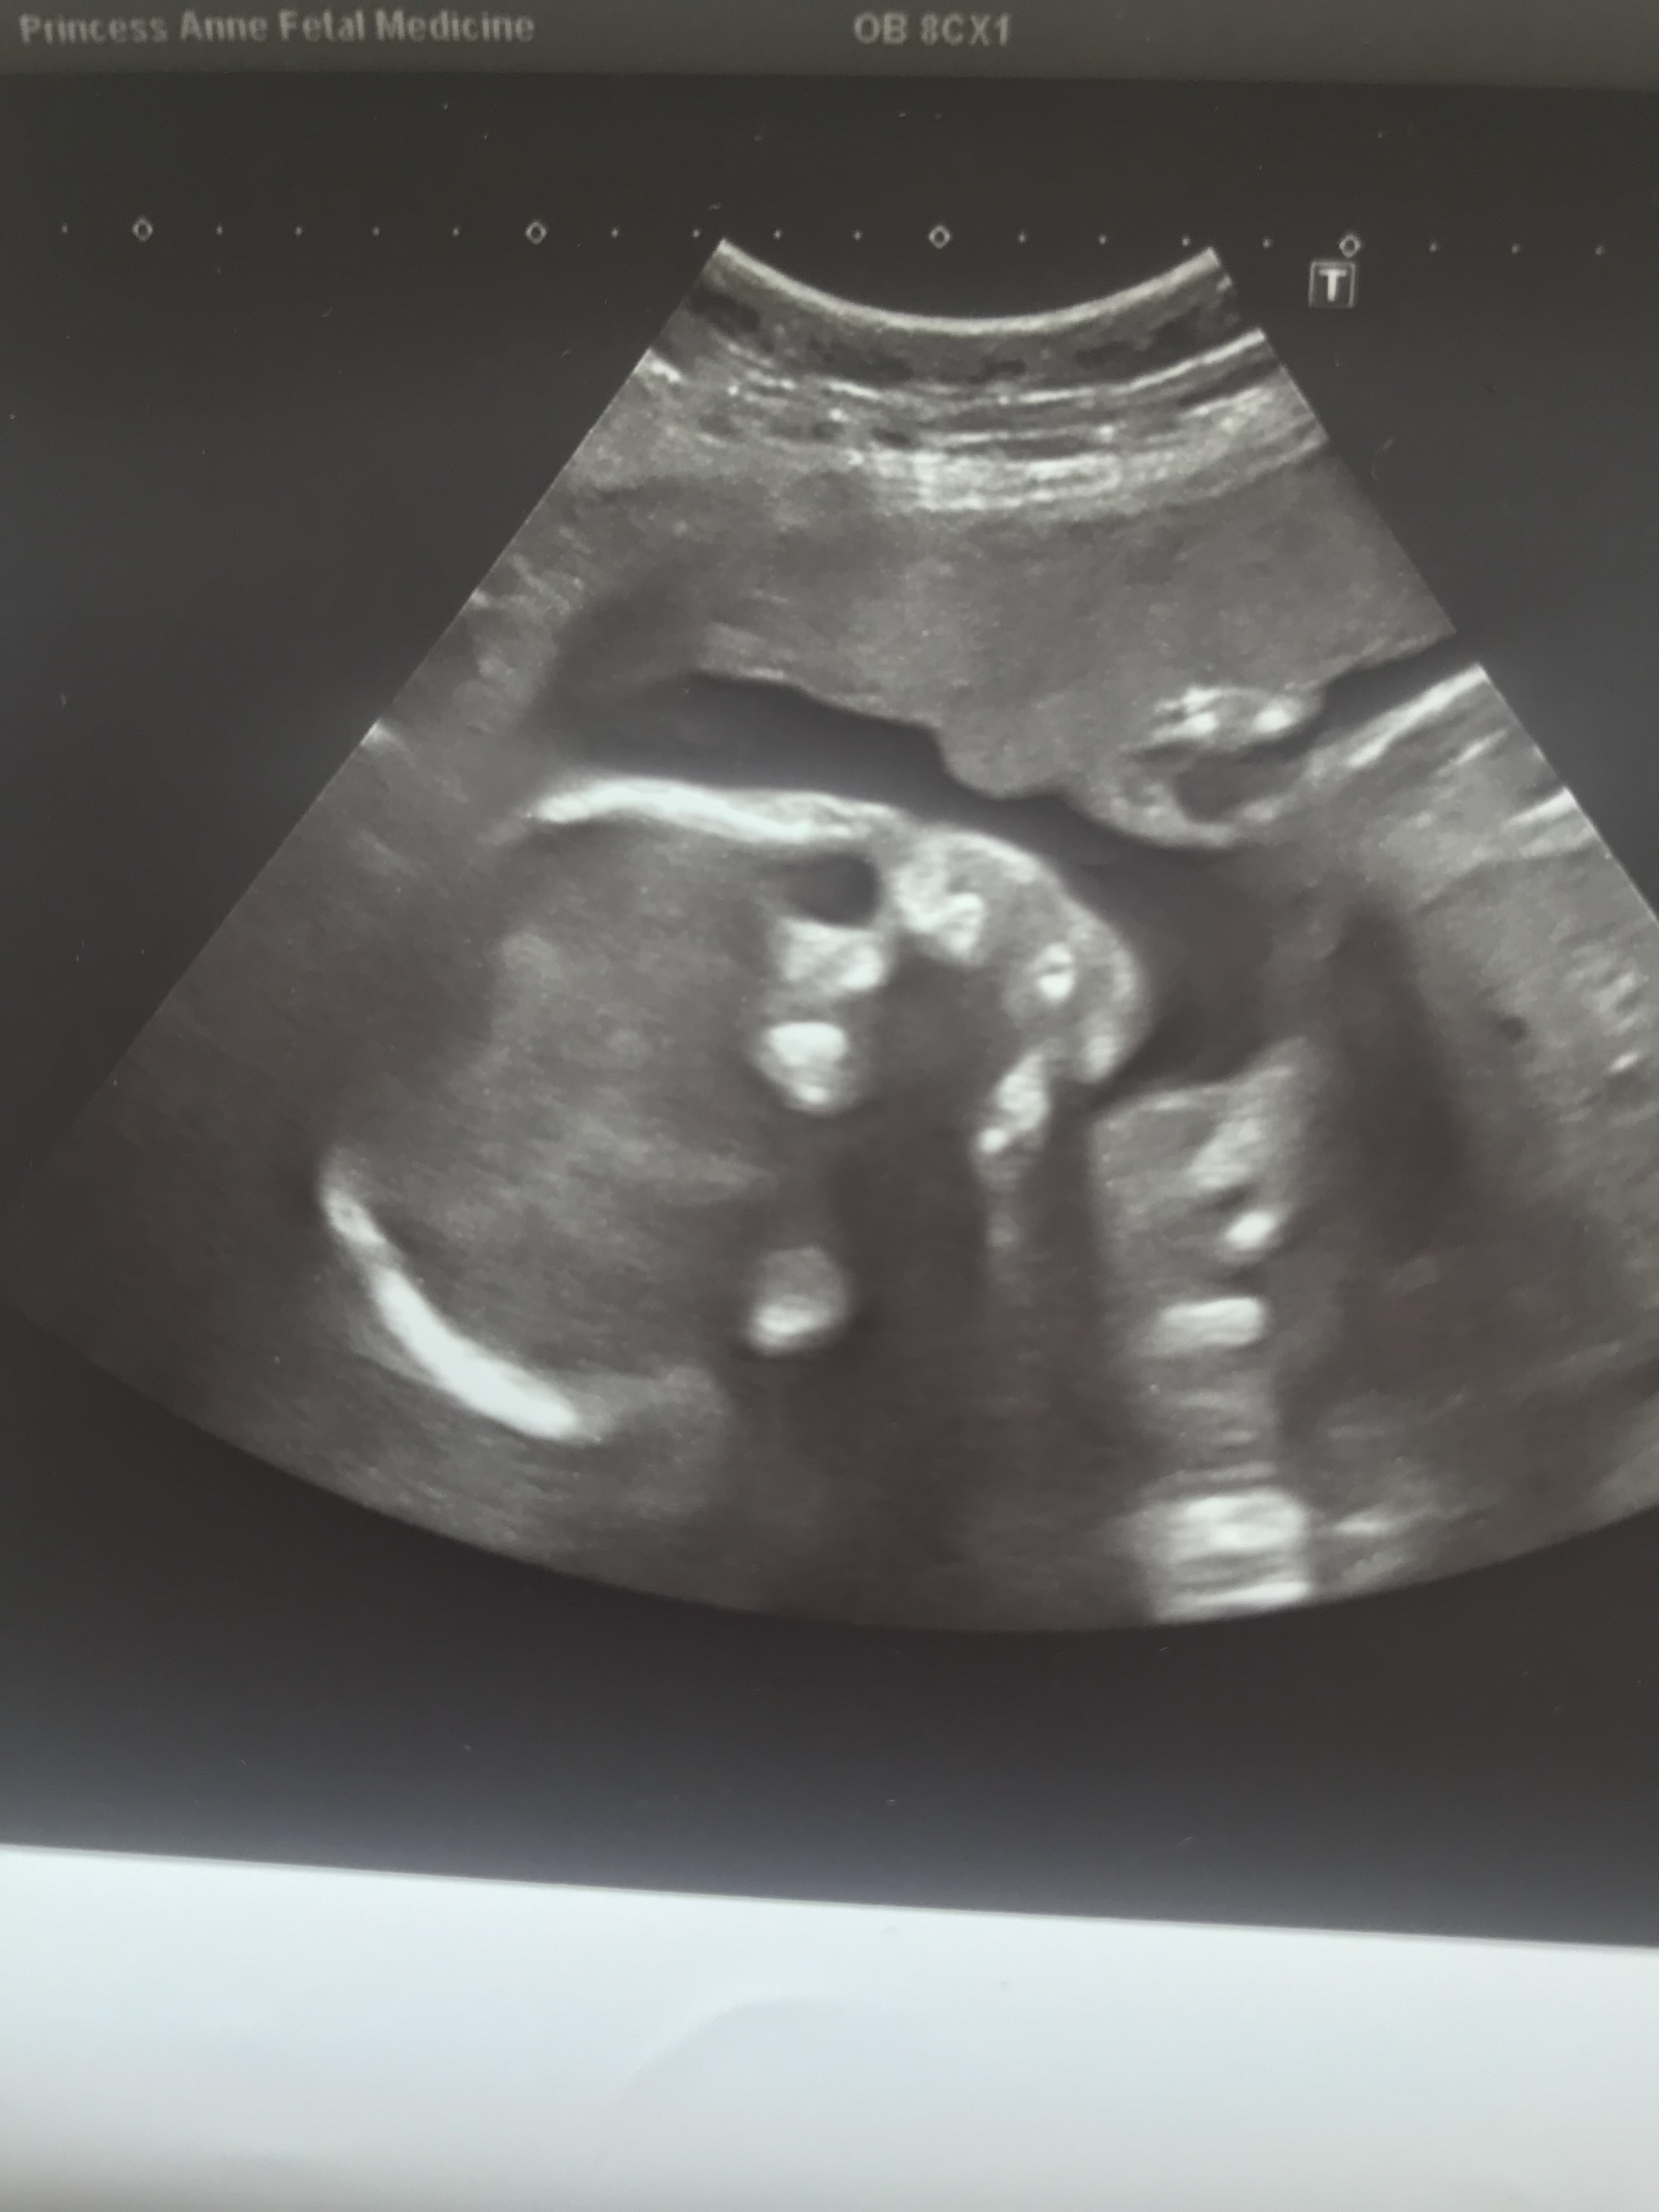

Romeo was in an awkward position so they sent me off for a walk when we came back into the room to be scanned again I noticed they were spending a lot of time looking at his heart, it was at this moment I started to get that awful gut feeling that something was wrong. “It might just be the way he is laying and we can’t get a clear view of his heart. I would rather get a second opinion on this” the sonographer said. We were escorted to one of the quiet rooms in the unit whilst we awaited a midwife to come in and explain more. “We’ve referred you to Southampton for the cardiologist to have a better look at the baby’s heart, we don’t know whether it’s the way he is laying or if there is a problem with his heart so we would rather get a second opinion from the Fetal medicine unit there.” I burst in to tears, this was so vague I didn’t know what it could mean as far as I was concerned my baby was fine I had heard his perfect little heart beating in my 16 week midwife appointment and now I’m being told there could be a problem. Automatically you just fear the worst and when I got home that night sure enough I started googling the hell out of heart problems picked up in the 20 week scan, probably not the best idea but I just wanted to know there and then instead of waiting 2 days.